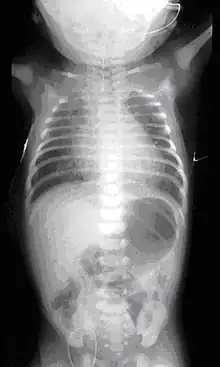

| Common anatomical types of esophageal atresia a) Esophageal atresia with distal tracheoesophageal fistula (86%), Gross C. b) Isolated esophageal atresia without tracheoesophageal fistula (7%), Gross A. c) H-type tracheoesophageal fistula (4%), Gross E.[1] | |

On plain X-ray, a feeding tube will not be seen pass through the esophagus and remain coiled in the upper oesophageal pouch.[8]

If any of the above signs/symptoms are noticed, a catheter is gently passed into the esophagus to check for resistance. If resistance is noted, other studies will be done to confirm the diagnosis. A catheter can be inserted and will show up as white on a regular x-ray film to demonstrate the blind pouch ending. Sometimes a small amount of barium (chalk-like liquid) is placed through the mouth to diagnose the problems. However, performing such an oral contrast study is not advised due to a risk of aspiration.[27]